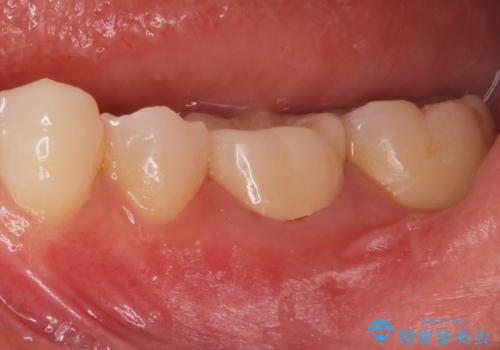

形を整えて型取りをし、ジルコニアクラウンを装着しました。

- ジルコニアクラウンスタンダード・仮歯 12.1万円費用は治療当時の料金となります

被せ物が入りました。

根管治療が終わった歯は被せ物を装着しないと細菌が根管内に侵入し根の再発のリスクが増えるため早急に被せ物を入れる事をお勧めします。